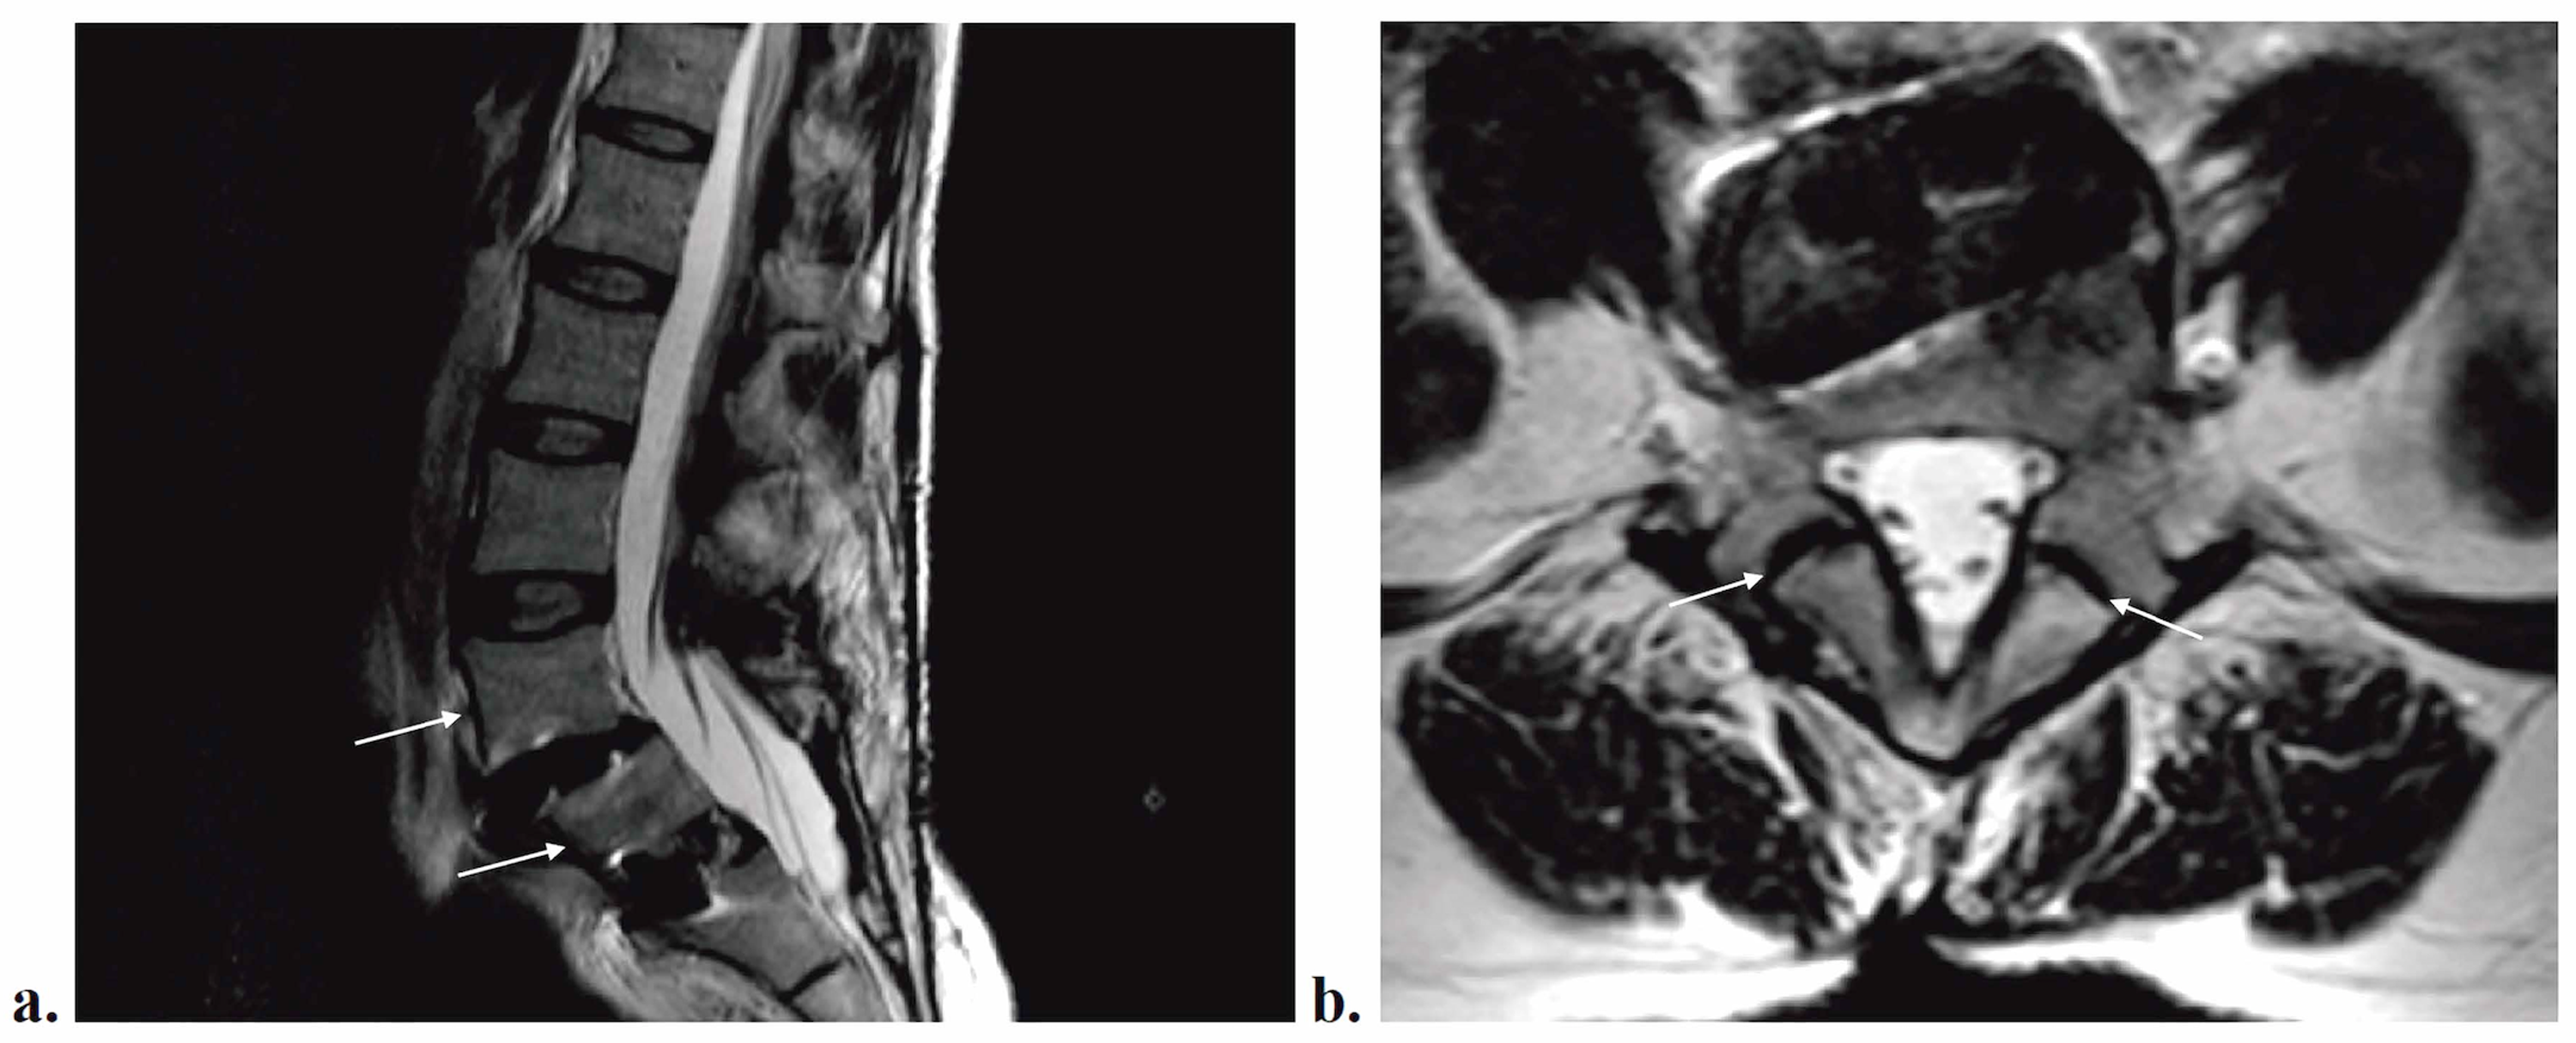

Lumbar Spine Mri Scan Taken Four Days After Posterior Lumbar And… |  Download Scientific Diagram Source: researchgate.net